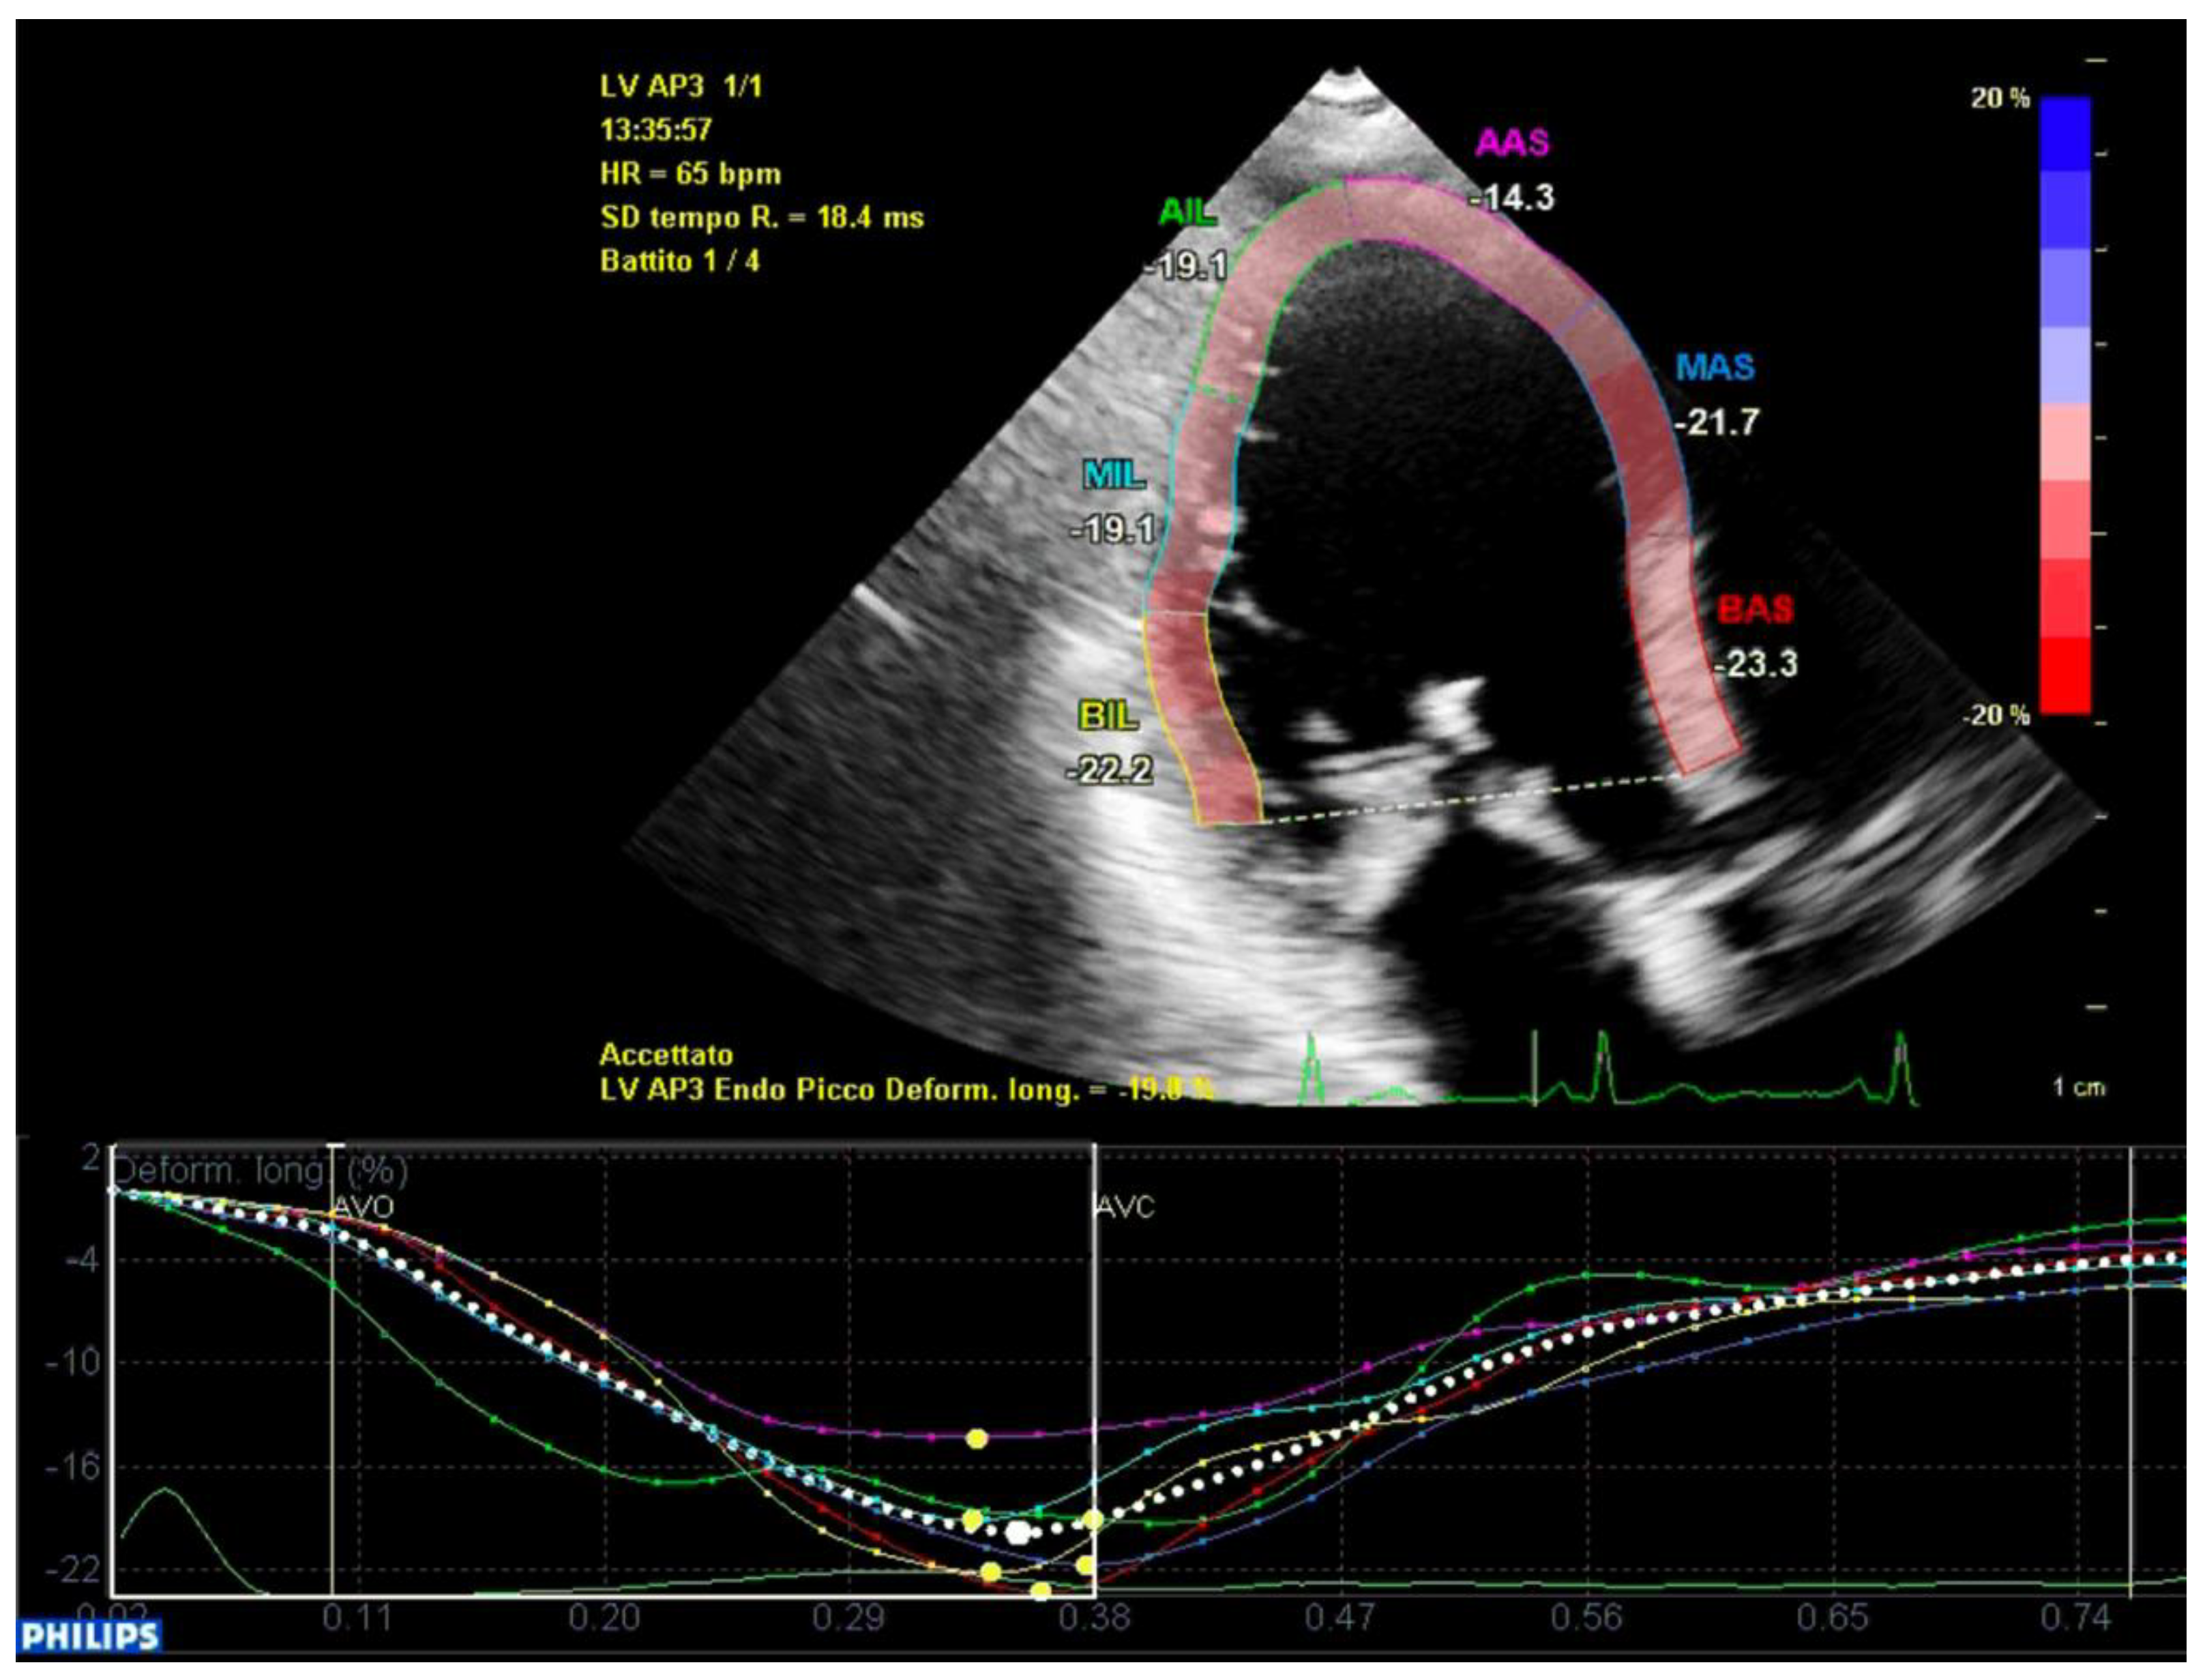

In the speckle tracking analyses, the longitudinal strain of single segments was similar between the two groups. The transversal shift, which was measured with speckle tracking, did not result significantly different between the cases and the controls. The strain pattern analyses highlighted the presence of a double peak pattern in both populations, both for longitudinal and transversal motions, but the incidence was similar between the two groups.

Mechanical dispersion calculated with speckle tracking analysis did not differ significantly between the two groups when it was measured globally, including all of the 18 segments of the left ventricle (ICD-MVP: 67.4 ± 23 ms, A-MVP: 70.0 ± 33 ms; p = 0.80).

When it was analyzed by single segments (basal, middle and apical), the mechanical dispersion of the apical segments did not differ between the two groups, while the basal and middle segments showed each an increased mechanical dispersion in the ICD-MVP group that did not reach statistical significance when it was analyzed alone (basal or middle), but it was statistically significant when it was analyzed in a combined way (ICD-MVP: 117 ± 31 ms, A-MVP: 76 ± 48 ms; p = 0.03).

In conclusion, the variables that were identified as the predictors of major arrhythmic events with the highest AUC (>0.80) within our high-risk population of arrhythmic MVP patients were the AML length (measured as shown in Figure 7), the S3 of the inferolateral basal segment and the mechanical dispersion of the basal and mid-ventricular segments calculated with speckle tracking analysis (Figure 8 and Figure 9).

Figure 9. Global longitudinal strain in a patient from the A-MVP group. Mechanical dispersion is lower as peak systolic shortening times present lower variability.